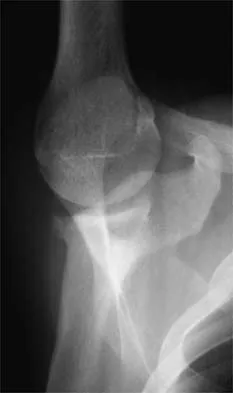

Figure 37 shows the radiograph of a 23-year-old football player who sustained a blow to the anterior aspect of his shoulder. Examination reveals pain and limited rotation. He is unable to flex the arm above the shoulder. Management should include which of the following studies?

Explanation